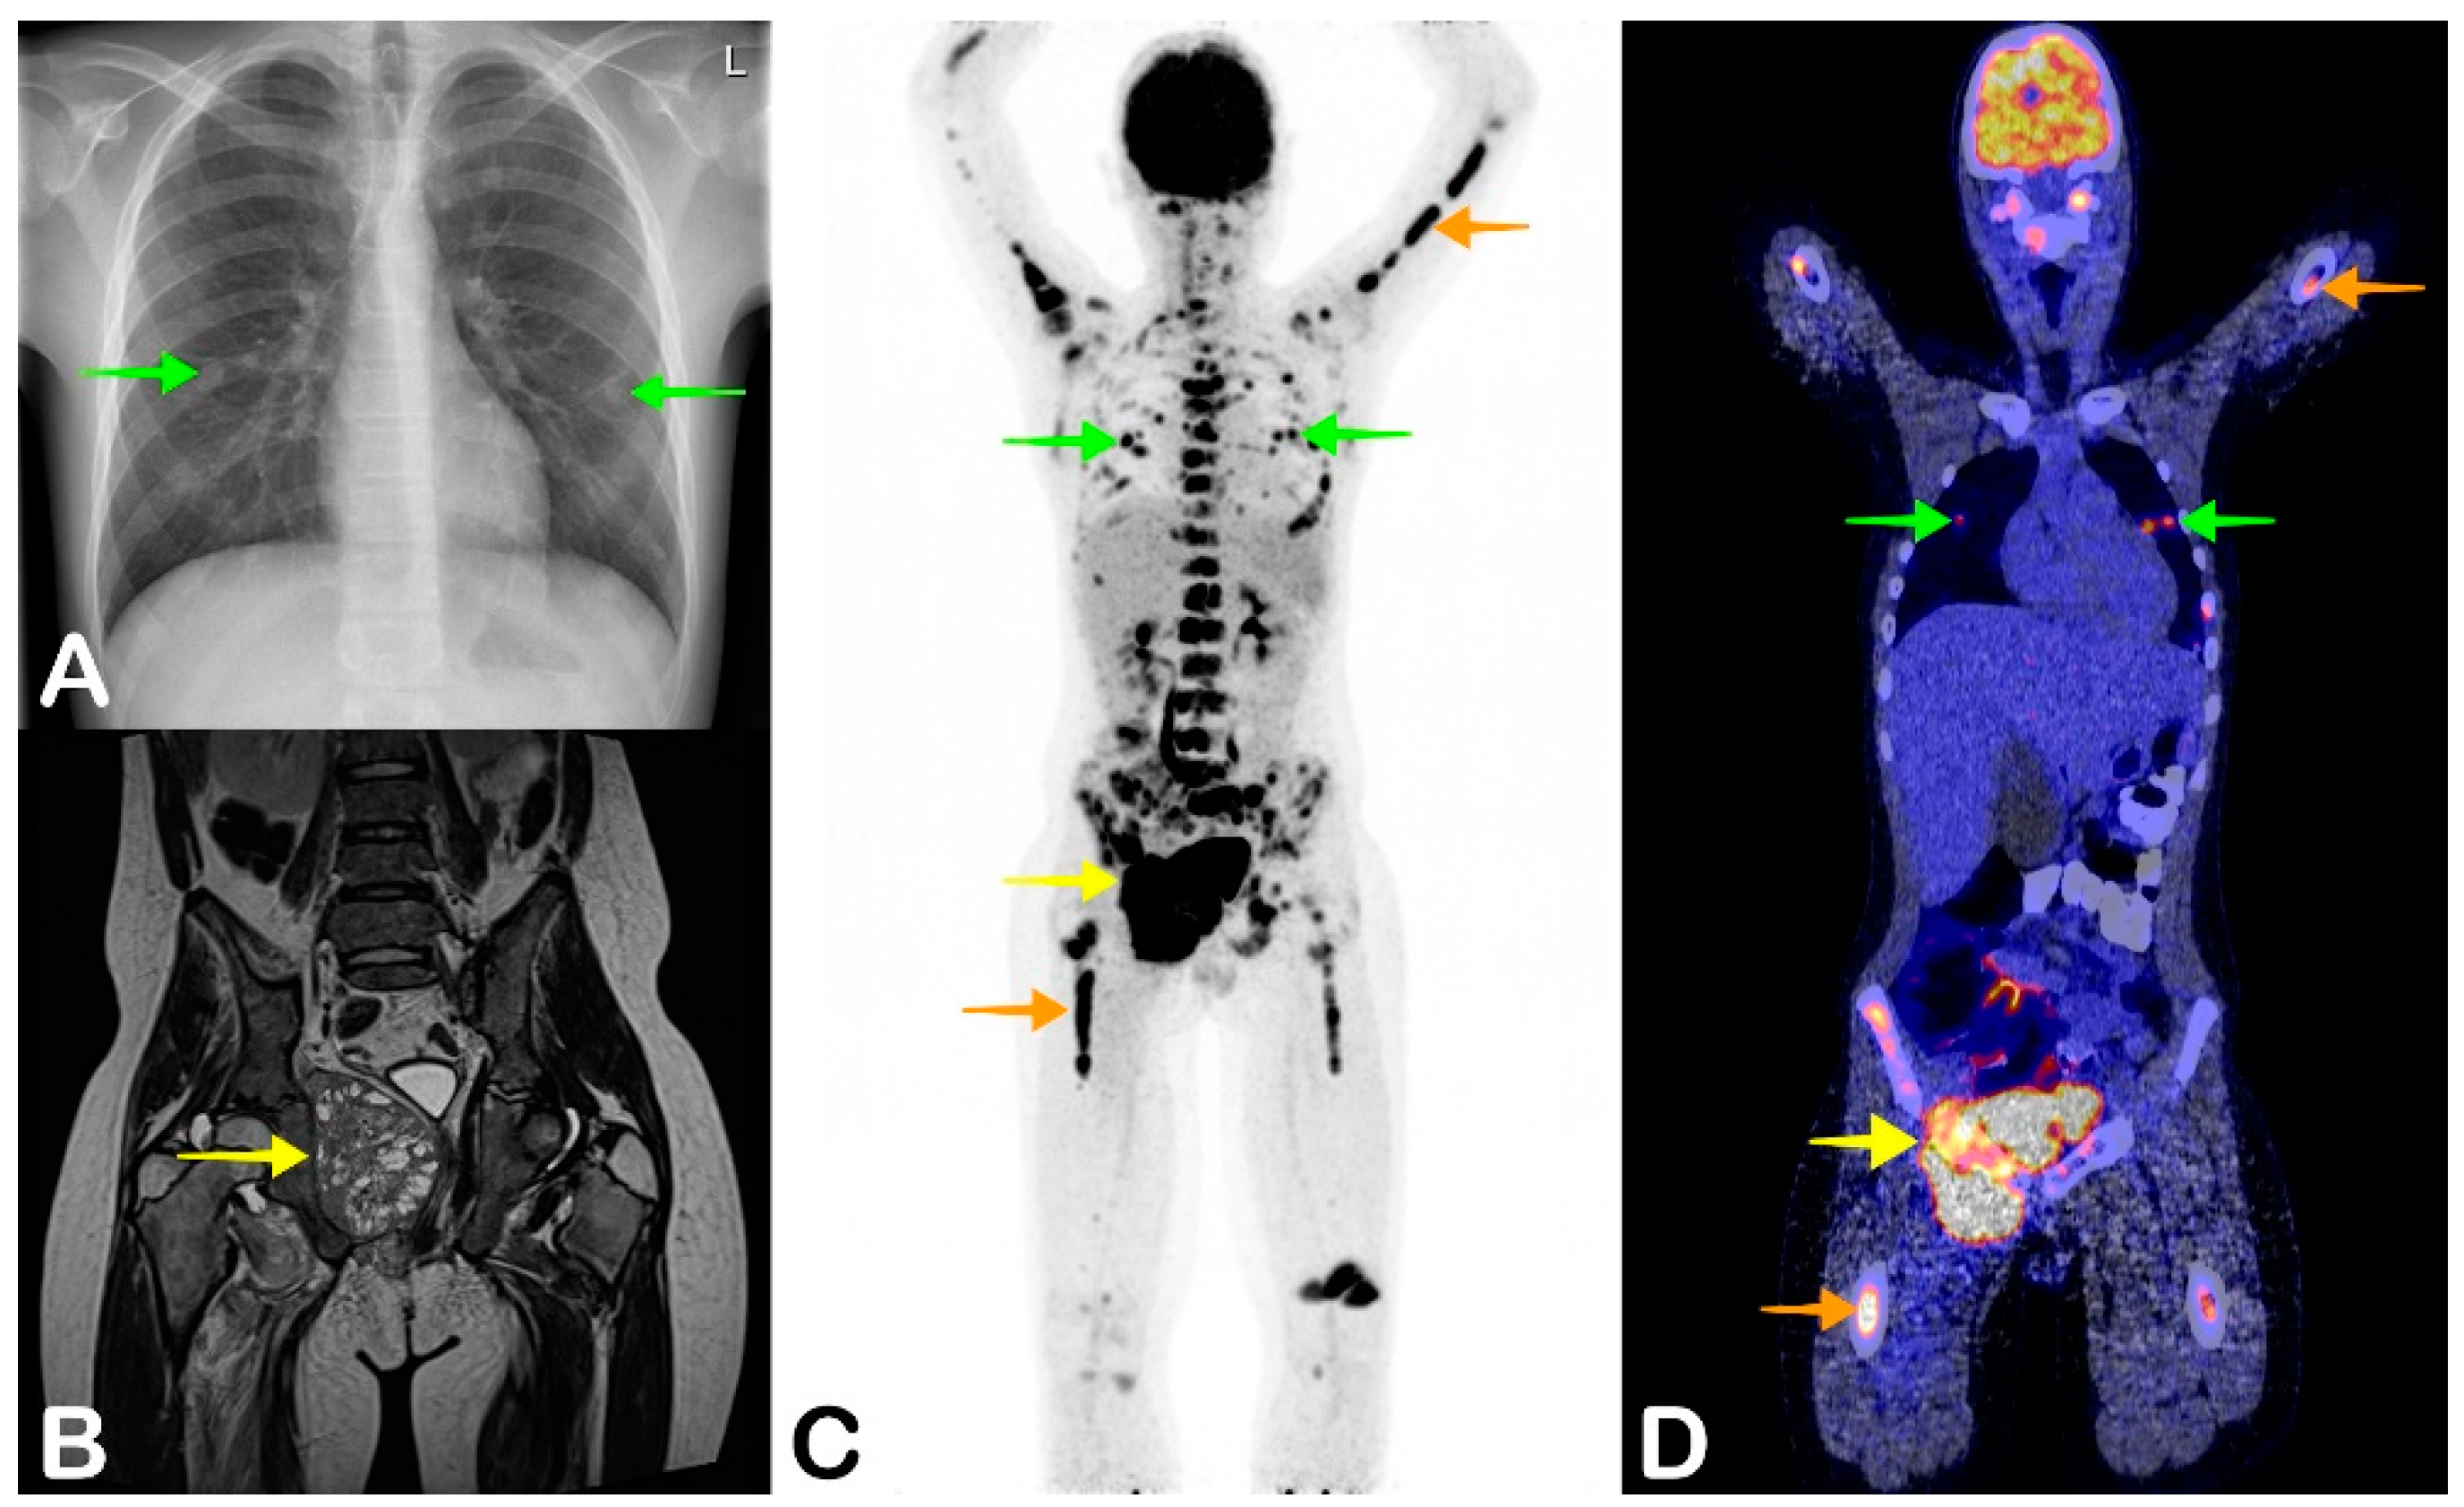

2.5. Spondylodiscitis

- Smids, C.; Kouijzer, I.J.E.; Vos, F.J.; Sprong, T.; Hosman, A.J.F.; De Rooy, J.W.J.; Aarntzen, E.H.J.G.; De Geus-Oei, L.-F.; Oyen, W.J.G.; Bleeker-Rovers, C.P. A comparison of the diagnostic value of MRI and 18F-FDG-PET/CT in suspected spondylodiscitis. Infection 2017, 45, 41–49. [Google Scholar] [CrossRef]

- Altini, C.; Lavelli, V.; Niccoli-Asabella, A.; Sardaro, A.; Branca, A.; Santo, G.; Ferrari, C.; Rubini, G. Comparison of the Diagnostic Value of MRI and Whole Body 18F-FDG PET/CT in Diagnosis of Spondylodiscitis. J. Clin. Med. 2020, 9, 1581. [Google Scholar] [CrossRef]